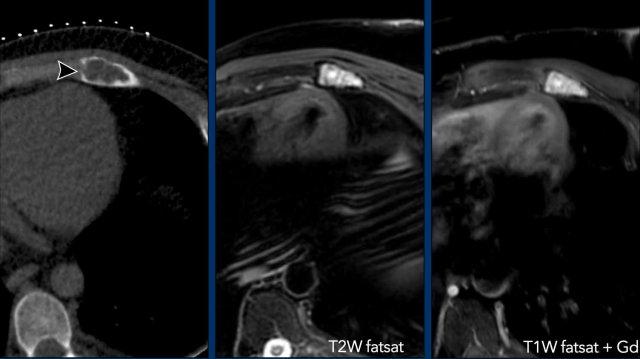

Hình ảnh

Ví dụ về một ACT tăng cường chậm (đường màu cam), hơn 10 giây sau động mạch (đường màu xanh lam).

Khối u sụn ở xương ức với phù nề quanh tổn thương và ngấm thuốc dạng vách-nốt.

Các hình ảnh tưới máu cho thấy khối u ngấm thuốc nhanh (vùng ROI và đường cong màu cam), trong vòng 8 giây sau động mạch chủ (vùng ROI và đường cong màu xanh dương).

Vùng ROI và đường cong màu hồng đại diện cho thành phần nhầy không ngấm thuốc.

Tổn thương này đã được cắt bỏ.

Chẩn đoán cuối cùng: Sarcoma sụn độ I (CS-I) ở xương ức